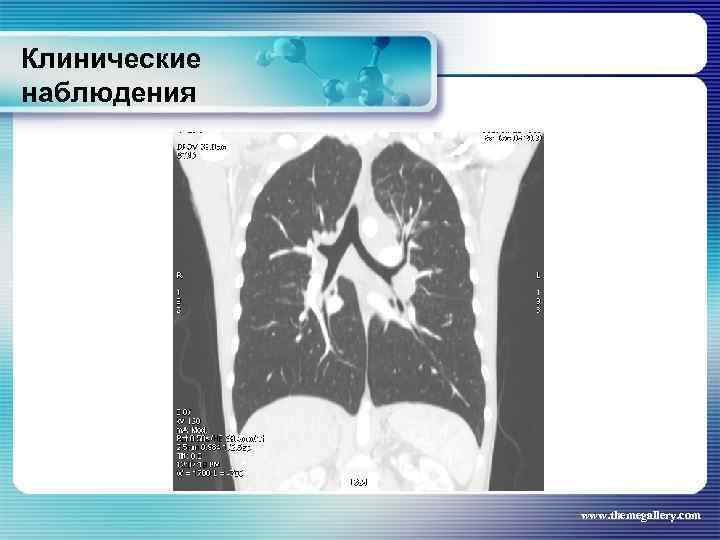

Клинические наблюдения Больной М. , 22 лет Заболел в январе 2010 года, когда появился мучительный кожный зуд, похудание, прогрессивный рост лимфатических узлов на шее, затрудненное дыхание. Самостоятельно обратился в поликлинику, направлен в гематологическое отделение. Выполнена биопсия шейного лимфатического узла: Лимфома Ходжкина. , нодулярный склероз Grade I. Уже отделении появилась лихорадка. При лабораторном обследовании выявлены признаки выраженной активности процесса. Результаты лучевого обследования: www. themegallery. com

Клинические наблюдения Больной М. , 22 лет Заболел в январе 2010 года, когда появился мучительный кожный зуд, похудание, прогрессивный рост лимфатических узлов на шее, затрудненное дыхание. Самостоятельно обратился в поликлинику, направлен в гематологическое отделение. Выполнена биопсия шейного лимфатического узла: Лимфома Ходжкина. , нодулярный склероз Grade I. Уже отделении появилась лихорадка. При лабораторном обследовании выявлены признаки выраженной активности процесса. Результаты лучевого обследования: www. themegallery. com

Клинические наблюдения www. themegallery. com

Клинические наблюдения www. themegallery. com

Клинические наблюдения www. themegallery. com

Клинические наблюдения www. themegallery. com

Клинические наблюдения www. themegallery. com

Клинические наблюдения www. themegallery. com

Клинические наблюдения www. themegallery. com

Клинические наблюдения www. themegallery. com

Клинические наблюдения www. themegallery. com

Клинические наблюдения www. themegallery. com

Клинические наблюдения Больной М. , 22 лет По результатам обследования сформулирован клинический диагноз: лимфома Ходжкина, нодулярный склероз, Grade I, III В стадия с поражением подчелюстных, шейных, надключичных лимфатических узлов с обеих сторон, подмышечных, переднегрудных, парастернальных, внутригрудных и абдоминальных лимфатических узлов, средостения. Было проведено 8 циклов BACOPP, на фоне лечения осложнение: полинейропатия рук, а затем асептический некроз головки правой бедренной кости. На фоне терапии отмечена положительная динамика как лабораторных данных, так и результатов лучевого обследования. Констатирована ремиссия www. themegallery. com

Клинические наблюдения Больной М. , 22 лет По результатам обследования сформулирован клинический диагноз: лимфома Ходжкина, нодулярный склероз, Grade I, III В стадия с поражением подчелюстных, шейных, надключичных лимфатических узлов с обеих сторон, подмышечных, переднегрудных, парастернальных, внутригрудных и абдоминальных лимфатических узлов, средостения. Было проведено 8 циклов BACOPP, на фоне лечения осложнение: полинейропатия рук, а затем асептический некроз головки правой бедренной кости. На фоне терапии отмечена положительная динамика как лабораторных данных, так и результатов лучевого обследования. Констатирована ремиссия www. themegallery. com